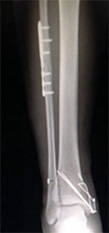

下腿骨折(すねの骨折)

バイクや自転車など交通事故で直接下腿をぶつけたりねじったりした時に生じる骨折です。

早期社会復帰のために手術が選択されることが多いものです。

• 画像:下腿骨折

(術前)

(術後)

• 画像:骨折観血的手術(下腿)髄内釘

骨折観血的手術(下腿)

髄内釘